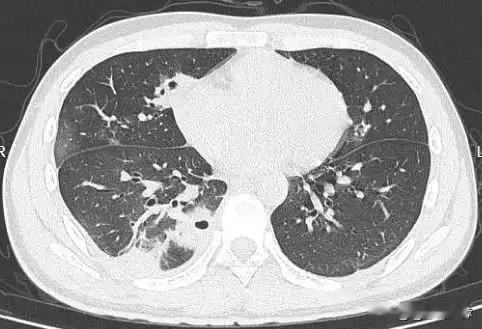

20岁男生挤痘险丧命!面部“危险三角区”为何如此危险? 近日,一则医疗案例引发广泛关注:一名20岁的大学生因随手挤掉脸上的一颗痘痘,竟引发严重感染,导致双肺出现十几个空洞,部分肺组织坏死。这听起来像是影视剧中的情节,却在现实中真实上演。 事件回顾:从一颗痘到肺部空洞 该学生在备考期间经常熬夜,某天发现面部冒出一颗红肿的痘痘。随手挤压后,痘痘不仅没有消退,几天后还出现持续高烧、剧烈咳嗽、呼吸急促等症状。就医后,CT检查结果令人震惊——他的肺部布满多个空洞,确诊为“血源性肺脓肿”。医生紧急使用强效抗生素治疗,最终将他从危险中抢救回来。 “危险三角区”的致命风险 医生指出,问题出在面部的 “危险三角区” ——即以鼻根为起点、嘴角连线为底形成的三角区域。这一区域血管丰富,且有一个致命的解剖特点:缺乏静脉瓣。 静脉瓣就像是血管中的“单向阀门”,能防止血液逆流。而危险三角区的静脉直通颅内的重要血管,且没有这层保护。挤压痘痘时,外力会将细菌(如金黄色葡萄球菌等)推入血管,细菌随血液“逆流而上”,进入颅内或肺部,引发: · 颅内感染:可能导致脑膜炎、脑脓肿 · 肺部脓肿:细菌通过血液播散至肺部,形成空洞 · 败血症:全身感染,危及生命 年轻人成高危群体,这些习惯要警惕 类似案例近年来并不少见,尤其在年轻人中高发,常与以下因素有关: · 熬夜、压力大导致免疫力下降 · 用手或不洁工具挤痘 · 忽略面部清洁与伤口护理 安全祛痘指南 医生建议,面对痘痘务必牢记: 1. 管住手:绝不随意挤压,尤其是“危险三角区” 2. 温和清洁:使用适合的洁面产品,保持面部清洁 3. 局部用药:可选用含维A酸、水杨酸或抗菌成分的外用药膏 4. 及时就医:若痘痘反复发作、红肿疼痛,应寻求皮肤科医生帮助 5. 调整生活习惯:避免熬夜、高糖饮食,保持健康作息 专家提醒 皮肤科专家强调,面部痘痘是常见的毛囊皮脂腺炎症,正确处理通常并无大碍,但错误的挤压行为可能“小题大做”,让小小痘痘酿成全身危机。若挤痘后出现发热、头痛、咳嗽等异常症状,必须立即就医。